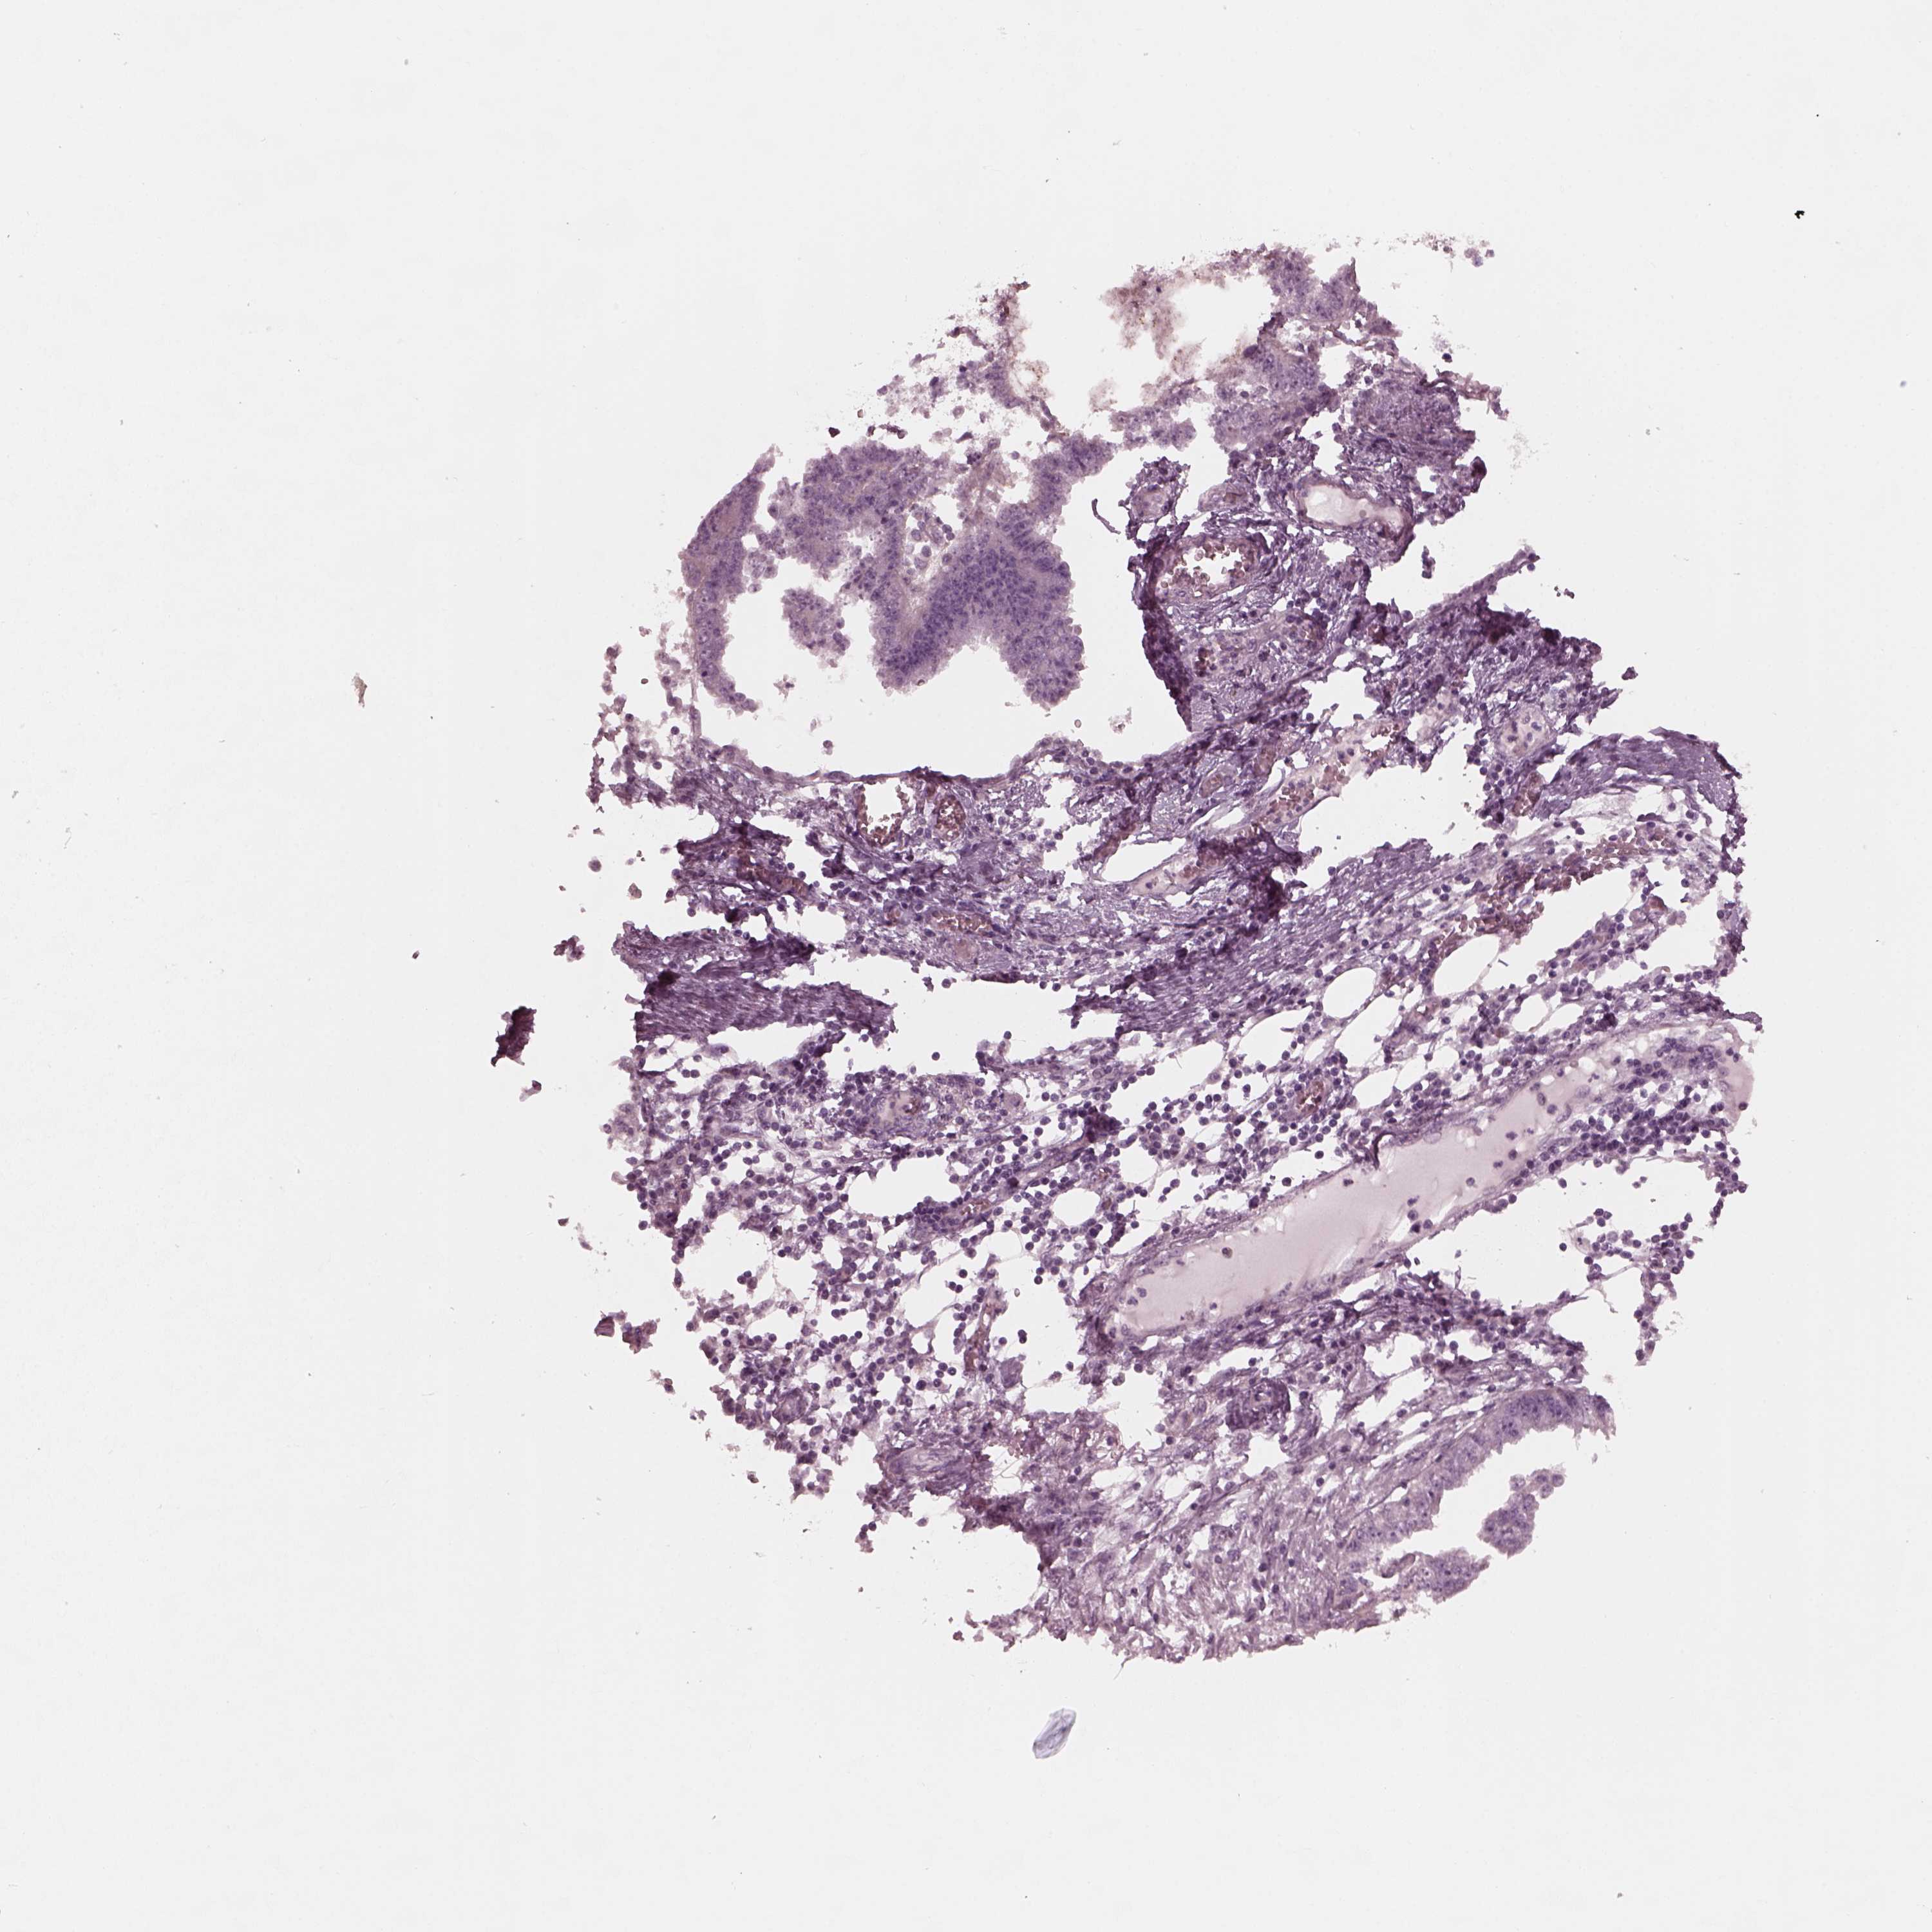

ENDOMETRIAL CANCER - Protein expressioni

A mouse-over function shows sample information and annotation data. Click on an image to view it in a full screen mode. Samples can be filtered based on level of antibody staining by selecting one or several of the following categories: high, medium, low and not detected. The assay and annotation is described here.

Note that samples used for immunohistochemistry by the Human Protein Atlas do not correspond to samples in the TCGA dataset.

Antibody stainingi

Antibody staining in the annotated cell types in the current human tissue is reported as not detected, low, medium, or high, based on conventional immunohistochemistry profiling in selected tissues. This score is based on the combination of the staining intensity and fraction of stained cells.

Each image is clickable and will lead to virtual microscopy that enables deeper exploration of all samples and also displays staining intensity scores, fraction scores and subcellular localization as well as patient and tissue information for each sample.

Antibody HPA038811

Staining

High

Medium

Low

Not detected

Intensity

Strong

Moderate

Weak

Negative

Quantity

>75%

75%-25%

<25%

None

Location

Nuclear

Cytoplasmic/membranous

Cytoplasmic/membranous,nuclear

Adenocarcinoma, NOS

Adenocarcinoma, metastatic, NOS